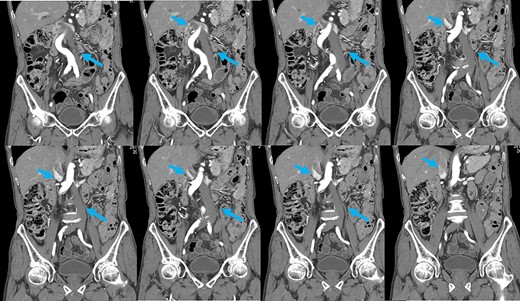

Preoperative computed tomography (CT) revealed a tumor in the sigmoid colon accompanied by some regional lymph node swelling (Fig. 1). It also showed that the IVC ascended vertically along the left side of the abdominal aorta. After connecting with the left renal veins, the left-sided IVC crossed the abdominal aorta anteriorly to join the normal prehepatic segment of the IVC (Figs 2 and 3). Coronal CT showed that the descending colon misplaced at the abdominal midline and the sigmoid colon in the right upper abdomen (Fig. 4). The preoperative diagnosis was thus sigmoid colon cancer with left-sided IVC and PDM.

Coronal reformation of the CT image shows precisely how the left-sided IVC (arrows) ascended vertically along the left side of the abdominal aorta and crossed anterior to the aorta.

After coronal reformation, the CT images show that the descending colon was at the midline of the abdomen (arrowheads), and the sigmoid colon was in the right upper abdomen (arrows).

PDM is a developmental anomaly characterized by failure of the descending mesocolon mesentery to fuse with the posterolateral parietal peritoneum [2]. The non-fused mesentery is then responsible for considerable variations in the position of the descending mesocolon. In our case, the descending colon was at the abdominal midline, and the sigmoid colon was in the right upper abdomen. Coronal reformatted images obtained by multidetector CT (MDCT) proved useful for an accurate preoperative diagnosis of the malpositioned descending colon. It is widely accepted that MDCT is an effective technique for staging colon cancer preoperatively [10]. MDCT also allowed us to generate multiplanar coronal images, which depicted the location of the colon as it would appear during the surgery. Moreover, MDCT angiography can be used to evaluate the running direction of the vessels. Because it has been reported that the left colon and sigmoid colon arteries and the superior rectal artery often branch radially from the inferior mesenteric artery, and that a marginal vessel may run abnormally due to the unusual mesenteric adhesion [5], accurate evaluation of the arteries is important for safe lymph node dissection.